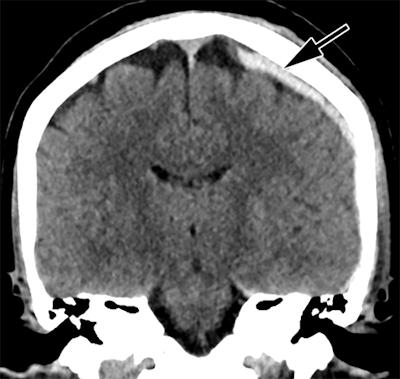

Head CT of intimate partner violence patient with left-sided parietal subdural hematoma (arrow).Caption and image courtesy of the RSNA.